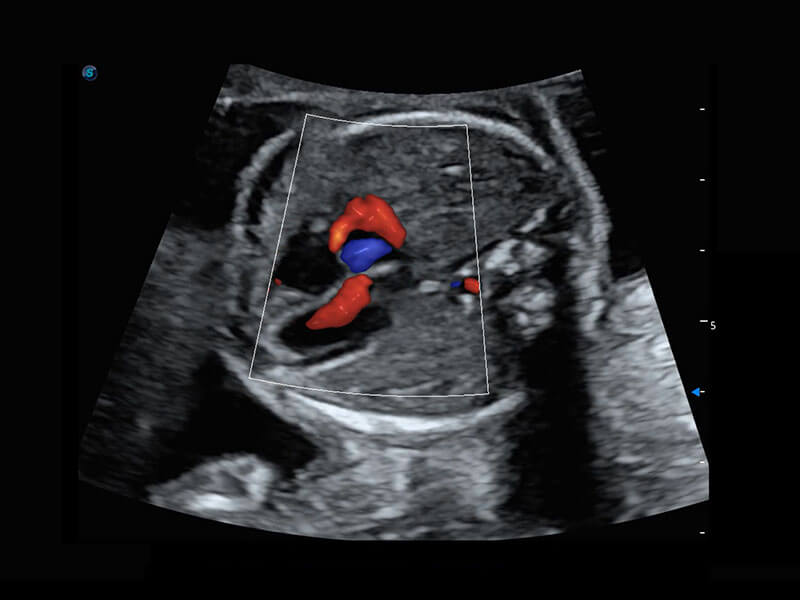

P60在胎兒早孕期超聲篩查中為您帶來(lái)優(yōu)異的圖像質(zhì)量。

早孕-胎心

P60搭載一系列胎兒心臟成像技術(shù),實(shí)現(xiàn)精細(xì)的胎兒心臟評(píng)估。

四腔切面

四腔心血流

右室雙出口

胎心容積成像